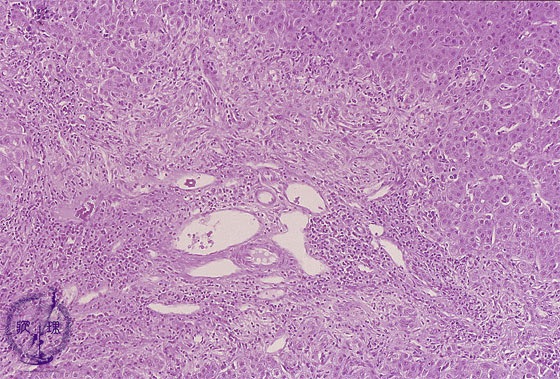

Microscopic image (HE stain, intermediate power): There is fibro-inflammatory portal expansion. Although portal artery, vein, and lymphatic vessels are conserved, bile ductules are absent and there is a periportal bile ductular reaction.